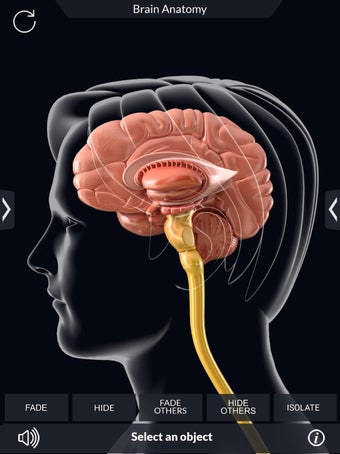

برنامج تشريح الدماغ Pro هو تطبيق تعليمي لدراسة تشريح الدماغ البشري. تم تصميم هذا التطبيق لكل من الطلاب الطبيين والجمهور العام. يتيح للمستخدمين استكشاف الدماغ من جميع الزوايا وعرض التشريح بطرق مختلفة. إنه أداة سهلة الاستخدام تتيح للمستخدمين تدوير 360 درجة والتكبير والتصغير وتحريك الكاميرا حول نموذج ثلاثي الأبعاد واقعي للغاية. يتيح للمستخدمين القدرة على تحديد الأجزاء وعرضها بالأشعة السينية وإخفائها وإظهارها وعرض الرسوم المتحركة في الوقت الحقيقي والرسم أو الكتابة على الشاشة ومشاركة لقطات الشاشة ونطق الصوت لجميع مصطلحات التشريح والمزيد. إنه تطبيق تعليمي مجاني.